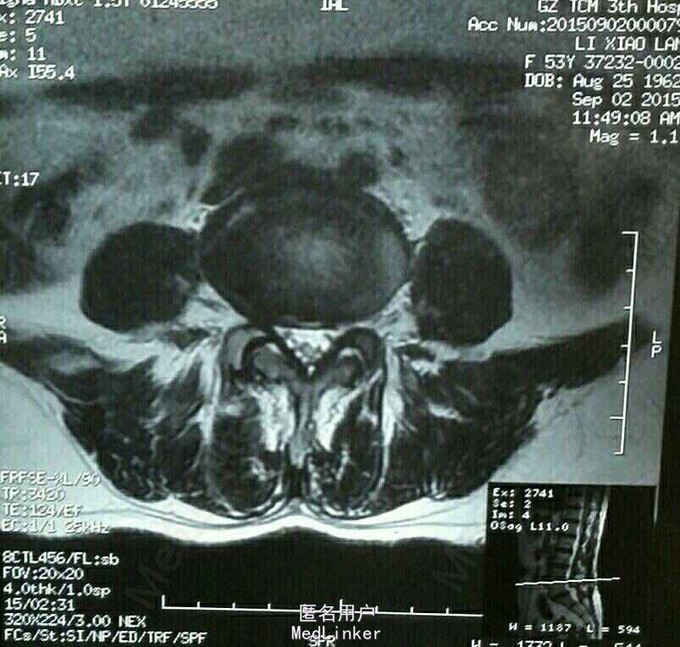

腰痛伴右下肢麻痛、乏力50余天,左下肢麻痛、乏力20天。50余天前无明显诱因出现右下肢麻痛、乏力,以麻木、乏力为主,20天前出现左下肢麻痛、乏力,行走200米时麻木加重、乏力明显,需休息后方能继续行走。经保守治疗半月,症状无明显改善,遂老我院就诊。

跛行步态,腰椎活动轻度受限,L5棘突及右侧脊旁压痛、叩痛,VAS评分腰痛3分,腿痛2分,JOA评分14分,ODI评分40%,余无明显阳性体征。外院MR提示:L5向前Ⅰ度滑脱并椎弓根峡部崩裂。我院腰椎动力位片示:1.腰椎退行性变,2. L5向前Ⅰ度滑脱并椎弓根峡部崩裂。

52岁女性患者,起病50余天,经保守治疗半月后症状无明显改善,腰椎MR及腰椎动力位片均提示:L5椎体滑脱。行L5/S1椎体融合术,术后患者双下肢麻痛及乏力明显缓解。对于腰椎滑脱的患者,经积极保守治疗后症状无明显改善者,应行手术治疗,手术效果较好。术后1月返院复查并复查腰椎X片。